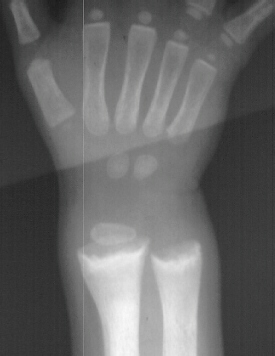

You

inform the adopted mother that she should expect to wait approximately

six months until a change in the child's condition is noted.

would plan to do tibial osteotomies to correct the severe varus

deformities in approximately 1 year after a good response the

nutritional management is seen.

It

is important to carefully monitor this girl's spine for kyphosis

and to a get a dental evaluation.

On

further testing the child was found to have elevated serum, BUN

and creatinine. It is now likely that all these changes are due

to chronic renal failure.

Rickets

always causes knee varus deformities.